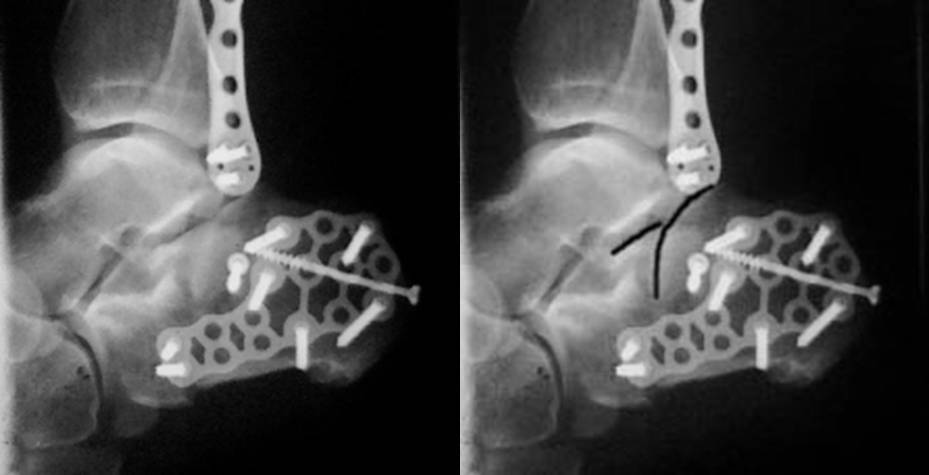

Точность репозиции суставной поверхности задней фасетки суставной поверхности пяточной кости на представленной вами рентгенограмме вызывает глубокие сомнения, так же как и конечный результат лечения в долгосрочной перспективе. По всей вероятности, у больного был перелом пяточной кости по классификации Sanders типа II A. Часть суставной поверхности задней фасетки, оставшаяся с sustentaculum пяточной кости (короткая линия на вложении, соответствующая субхондральному слоя репонированного фрагмента) находится на месте. А вот большая часть суставной поверхности так и осталась компримирована (длинная линия на вложении, соответствующая субхондральному слою компримированного фрагмента). При репозиции эти две линии должны совпадать. После репозиции, компримированный фрагмент следовало фиксировать к sustentaculum отдельным винтом (не всегда просто точно попасть). Пяточная пластина смещена к пяточному бугру, что не позволило фиксировать к ней самый проблемный участок пяточной кости – суставную поверхность. Не лишней здесь после репозиции была бы и костная пластика.